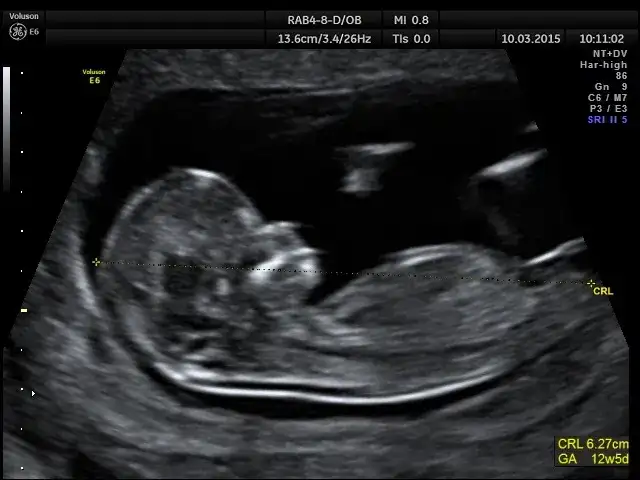

USG połówkowe (18-22 tydzień): Najpopularniejszy czas na wielką nowinę

Jeśli szukacie momentu, w którym poznanie płci dziecka jest najbardziej prawdopodobne i wiarygodne za pomocą USG, to z pewnością będzie to USG połówkowe. To badanie, wykonywane zazwyczaj między 18. a 22. tygodniem ciąży, jest najczęstszym i najbardziej komfortowym dla rodziców czasem na poznanie tej długo wyczekiwanej nowiny.

Dlaczego to badanie daje tak dużą pewność?

USG połówkowe daje wysoką pewność oceny płci, wahającą się w granicach 95-99%. Dlaczego tak jest? Na tym etapie ciąży narządy płciowe płodu są już na tyle rozwinięte i wyraźne, że doświadczony lekarz, dysponujący dobrym sprzętem i przy sprzyjającym ułożeniu dziecka, jest w stanie je zidentyfikować. Dziecko jest już też na tyle duże, że łatwiej je obejrzeć, a jednocześnie ma jeszcze wystarczająco dużo miejsca w macicy, by swobodnie się poruszać i przyjąć odpowiednią pozycję.